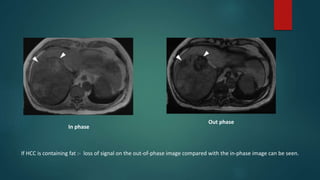

In phase

Out phase

If HCC is containing fat :- loss of signal on the out-of-phase image compared with the in-phase image can be seen.